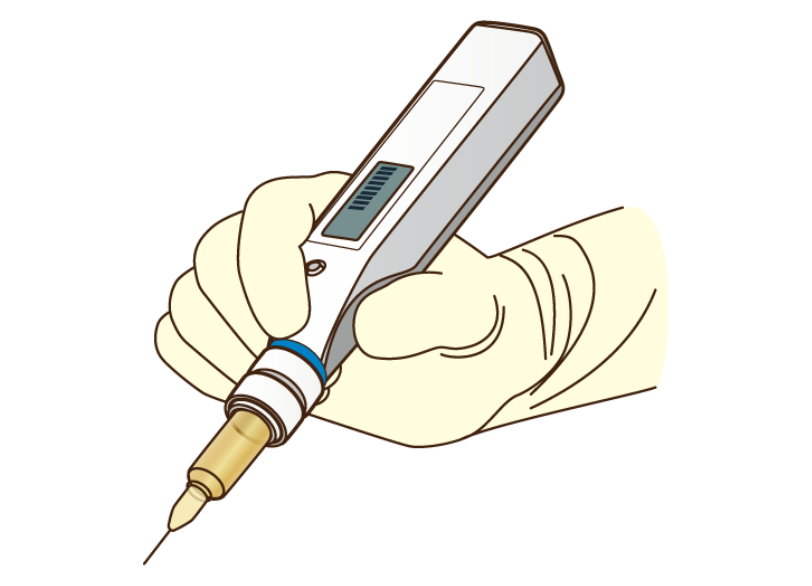

電動麻酔器の活用

麻酔液を注入する際の痛みは注入する圧力や速度のムラによって生じることがあります。

当院ではコンピューター制御によってゆっくりと一定の速度で麻酔液を注入できる「電動麻酔器」を使用しています。

これにより注入時の不快感を最小限に抑えることができます。